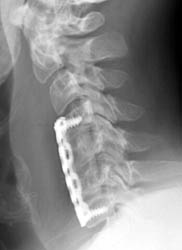

Screws and Graft Displacement

The patient is a 46-year-old male who had undergone the corpectomies of C5-6

and discectomies at C4-7 with anterior plate fusion and bone grafting for

cervical myelopathy resulting from cervical stenosis as well as kyphotic

deformity. Thereafter, the patient noted increased spasm of his right arm as

well as right leg. Work up revealed that the patient had dislodged the inferior

portion of the bone graft as well as the plate.

This post-operative radiograph suggests normal alignment of the bone graft

and fixation plate